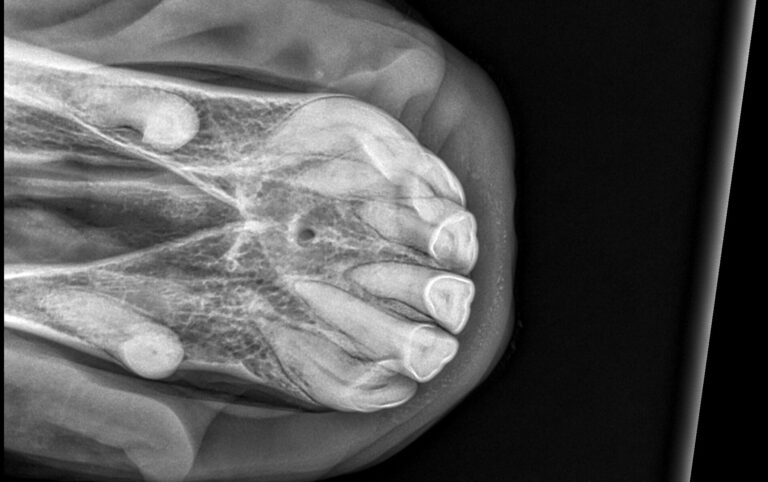

Als „Pferdezahnarzt“ biete ich professionelle Pferdezahnmedizin. Okklusionsoptimierung und sogenanntes „bit fitting“ (Anpassen von Trense und Reithalfter) sowie Zahnröntgen für Großpferde, Ponys und Esel.